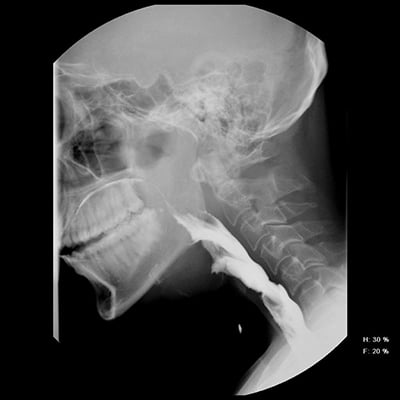

This module will help you achieve optimal images when performing cervical, thoracic, and lumbar spine examinations. Patient preparation and positioning are discussed, as well as technical settings and patient instructions. Descriptions and images of the expected anatomical structures are included, as well as image evaluation criteria.